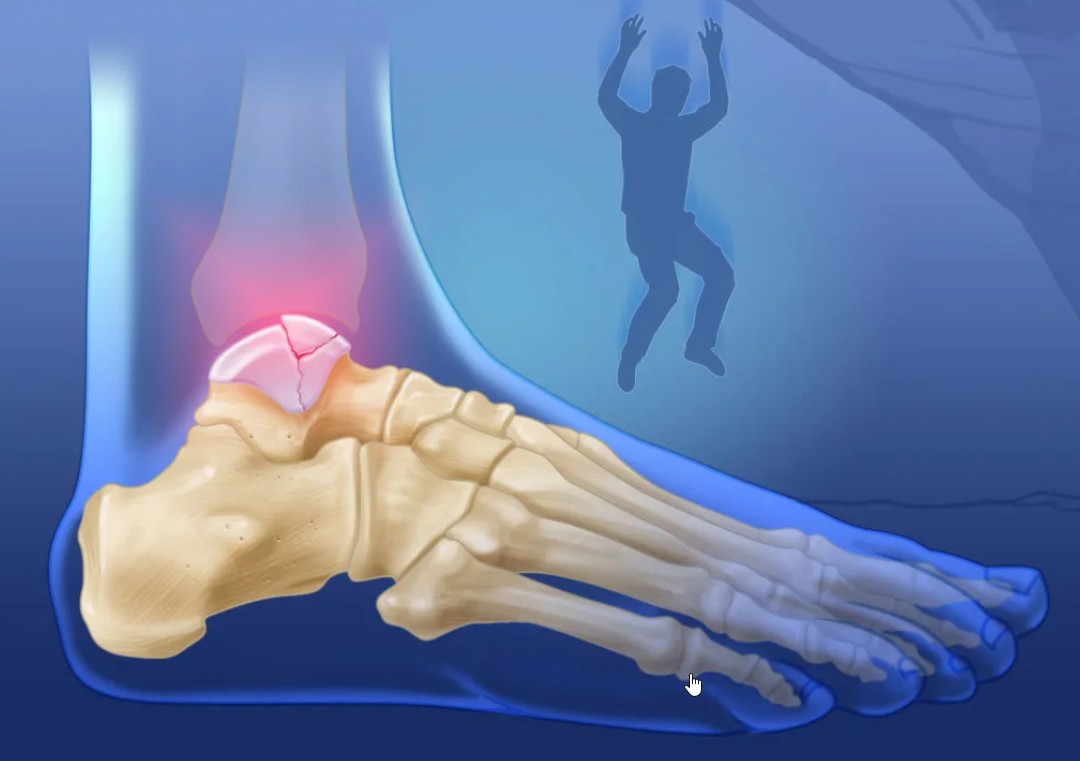

Такое повреждение является одним из самых распространённых среди травм стопы как у взрослых граждан, так и у детей. Это приводит к утрате рессорной функции стопы, в результате чего больной не имеет возможности наступать на ногу, а также испытывает сильную боль. При его получении следует как можно скорее обращаться за профессиональной помощью к докторам с целью получения качественного лечения и реабилитации для восстановления анатомической целостности повреждённой кости.

Основные симптомы перелома плюсневой кости

В каждом отдельном случае у больного тревожные симптомы и их интенсивность будут проявляться по-своему в зависимости от вида повреждения и его локализации, а также особенностей организма. Тем не менее обращаться к специалистам за помощью следует при появлении следующих признаков:

- Сильная боль, которая увеличивается при нагрузке на повреждённую стопу.

- Появление гематом и отёчности.

- Характерная хромота.

- Невозможность передвигаться самостоятельно.

- Больной не может опираться на повреждённую ногу.

- Деформация пальцев на стопе.

Появляется такая травма по самым различным причинам. Например, при ДТП, получении удара тяжёлым предметом, при чрезмерных и длительных нагрузках на стопу, в случае неудачного прыжка или при дегенеративно-дистрофическом изменении костной ткани. Вне зависимости от первопричин при такой травме следует незамедлительно обращаться за помощью к докторам.

Врач проведёт обследование, поставит точный диагноз, а затем на основании этого составит план лечения и восстановления. В процессе обследования применяется рентген, МРТ и КТ. Только такой подход поможет достичь полноценного выздоровления, возвращения к активной жизни и снизит риски развития осложнений. Для этого вы всегда можете обратиться за помощью в наш современный реабилитационный центр «Исток» в Беслане.